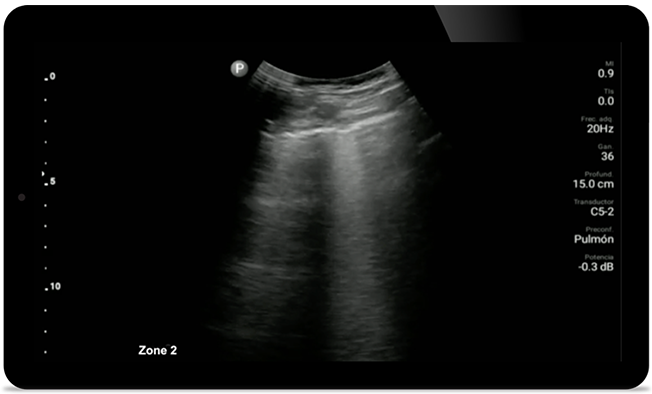

Lumify can help give results similar to a chest CT when evaluating pneumonia and adult respiratory distress syndrome.

• 12 to 4 MHz extended operating frequency range • Aperture size: 34mm • 2D, steerable color Doppler, M-mode, advanced XRES and multivariate harmonic imaging, SonoCT • High resolution imaging for shallow applications: soft tissue, vascular, superficial, musculoskeletal, and lung • Center line marker • USB-C transducer with replaceable cable